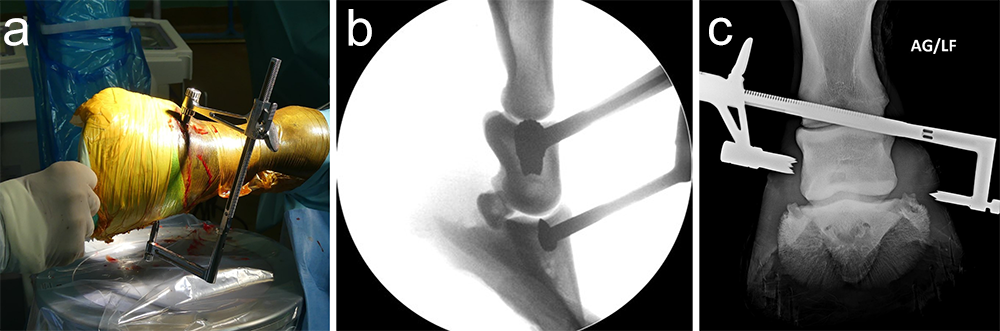

An articular fracture of the lateral wing of the distal phalanx was diagnosed at the track in this 3-year-old Standardbred racehorse, which was referred for surgery. Internal fixation was planned with a 5.5 mm cortex screw in lag fashion to restore and maintain articular congruency by fracture reduction and interfragmentary compression. Drill trajectory was planned with computed tomographic (CT) guidance with the horse awake and standing. Grids of barium paste dots were placed at proposed entry and projected exit sites. Once the ideal dot was selected from each grid the horse was anesthetized and the hoof prepared for surgery. The veterinary Screw Targeting Clamp (STC) was affixed to the hoof at the ideal dot in the entry and exit grids. Drilling, countersinking, measuring, tapping, and screw placement were achieved through the STC. The CT guidance and the STC allowed placement of the screw between the articular surface and vascular canal containing the terminal arterial arch, and in an orientation that resulted in accurate reduction instead of translation of the fracture fragment and parent bone.

A frontal plane fracture of the third carpal bone was diagnosed at the track in this 3-year-old Thoroughbred racehorse, which was referred for surgery. Internal fixation was planned with a 3.5 mm cortex screw in lag fashion. The Screw Targeting Clamp (STC) placement was guided using needles with radiographic and arthroscopic imaging. From skin incision to screw placement, lag screw fixation was achieved through the STC without movement or removal of the device.